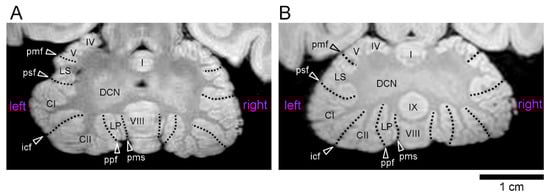

Figure 1.

Three-dimensional volume-rendered images of the cerebella of young adult cynomolgus monkeys. (A–C) Anterior, dorsal, and posterior views in the male cerebellum. (D–F) Anterior, dorsal, and posterior views in the female cerebellum. The cerebellar cortex was divided into five transverse domains: the left and right sides of the anterior zone (AZ) (vermal lobules I–V), central zone anterior (CZa; vermal lobule VI and lobules simplex), central zone posterior (CZp; vermal lobule VII, and the crura I and II regions of the ansiform lobules), posterior zone (PZ; vermal lobules VIII–IXa, and paramedian lobule), and nodular zone (NZ; vermal lobules IXb–X, paraflocculus and flocculus). The left and right sides are divided at midline, which was defined by the position of the cerebral longitudinal fissure. Dot lines delineate the intercrucial fissure (icf) and paramedian sulcus (pms). CI—crus I of ansiform lobule; CII—crus II of ansiform lobule; F—flocculus; LP—paramedian lobule; LS—lobulus simplex; PF—paraflocculus; pmf—primary fissure; psf—posterior superior fissure.

The volumes of the whole cerebellum and the five cerebellar transverse domains in male and female cynomolgus monkeys are summarized in Table 1. There was no statistically significant difference in the whole cerebellar volume between males (3441 ± 147 mm3) and females (3338 ± 204 mm3) according to Student’s t-test. The sexual differences in volume were not statistically significant when the cerebellum was divided into five transverse domains. We further estimated the volumes of the cerebellar hemispherical lobules, which could be delineated boundaries by cerebellar fissures/sulci, as shown in Figure 1 and Figure 2. The volumes did not differ between the sexes in the crura I and II regions of the ansiform lobules, paramedian lobule, and flocculus/paraflocculus by the Student’s t-test (Table 2).